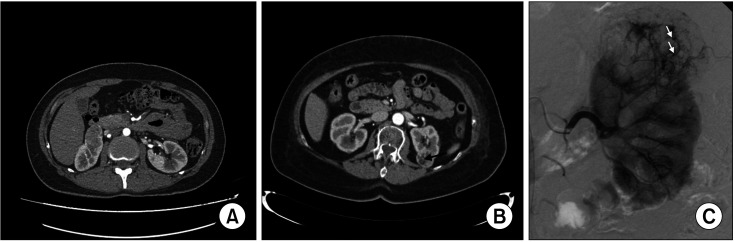

Results: A total of 150 patients were included. The median follow-up was 64.5 months (interquartile range [IQR] 25-102). Median tumor size at diagnosis was 14 mm (IQR 8-26). During follow-up, 12 patients (8.0%) required selective angioembolization, including 6 in whom the procedure was urgent due to spontaneous bleeding. At 5 years of follow-up, we found a 4.5% risk of HC and 3.6% of patients had a clinically significant growth rate of ≥3 mm/year. The existence of a rich blood supply (odds ratio [OR] 11.10, 95% confidence interval [CI] 1.68-23.54), and the size of AMLs at diagnosis (OR 1.02, 95% CI 1.01-1.04) were predictors for HC.

Conclusions: Renal AMLs have a minimal size progression and a very low risk of HC, allowing use of active surveillance as a first-line approach. Imaging features, such as the existence of a rich blood supply, could be useful in identifying patients at higher risk of bleeding for the purpose of risk-adapted decision making.